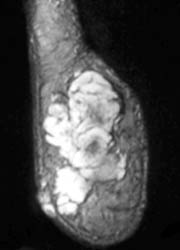

A rare low-grade soft tissue sarcoma that occurs at a mean age of 50 years. It often presents as a slowly growing painful and tender soft-tissue mass, usually affecting the extremities. 40 to 45 percent are metastatic lesions at the time of presentation. On CT or plain radiography, a soft tissue mass with ring, arc, stippled, and highly opaque calcifications may be noted. They most commonly are isointense to muscle on T1 and hyperintense (isointense to fat) on T2 W images. T1W post Gd images show contrast enhancement. Low signal intensity foci of calcification are present. They may mimic a cyst or myxoma.

64-year-old male with a painless soft tissue mass in the lateral aspect of the right heel. Plain radiograph demonstrates a densely calcified mass in this region. MR demonstrates this mass to be isointense on T1 and hyperintense on T2W images, with a central area of hypointense calcification.